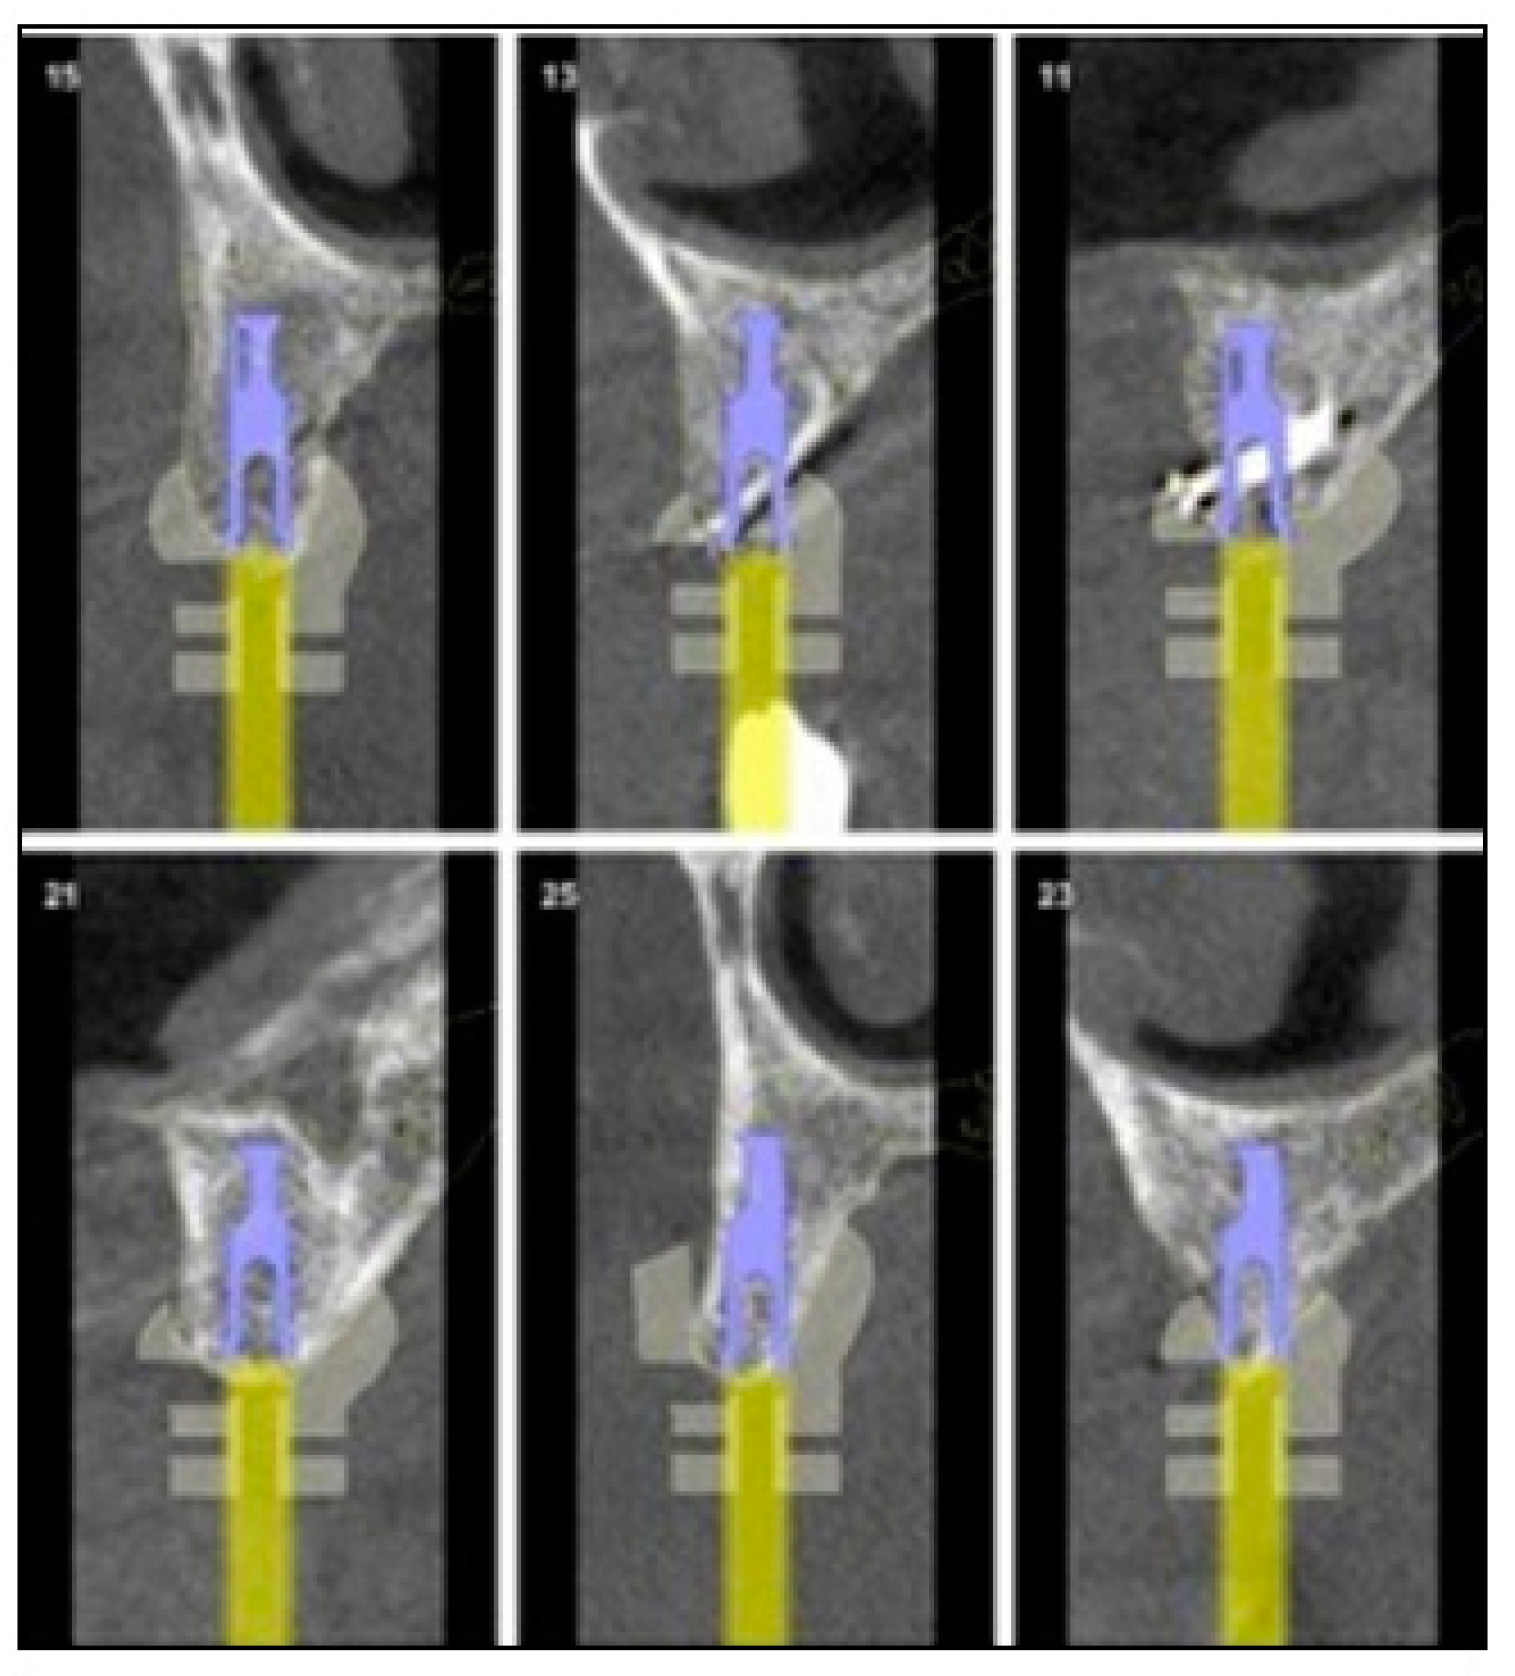

2.2. Surgical Phase